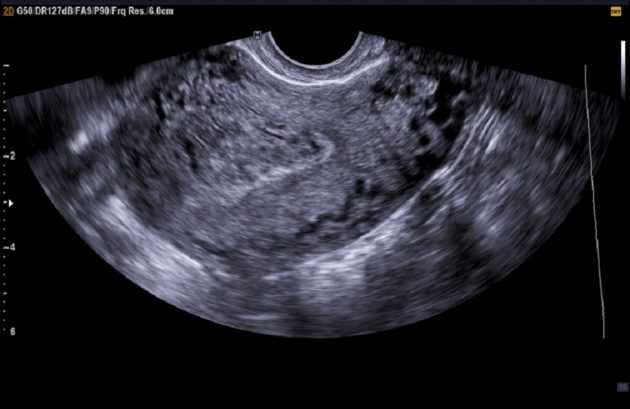

Врачебная помощь нужна и в том случае, если месячные продолжаются 14 дней, но не обильные. Гинеколог проводит осмотр. Это необходимо, чтобы определить характер выделений, их интенсивность и оценить состояние половых органов. Для уточнения причины патологии проводят УЗИ. Если по результатам указанных обследований проблему выявить не удается, назначают анализы крови. Проверить надо количество тромбоцитов, концентрацию эстрогена, тестостерон, пролактина, кортизола.